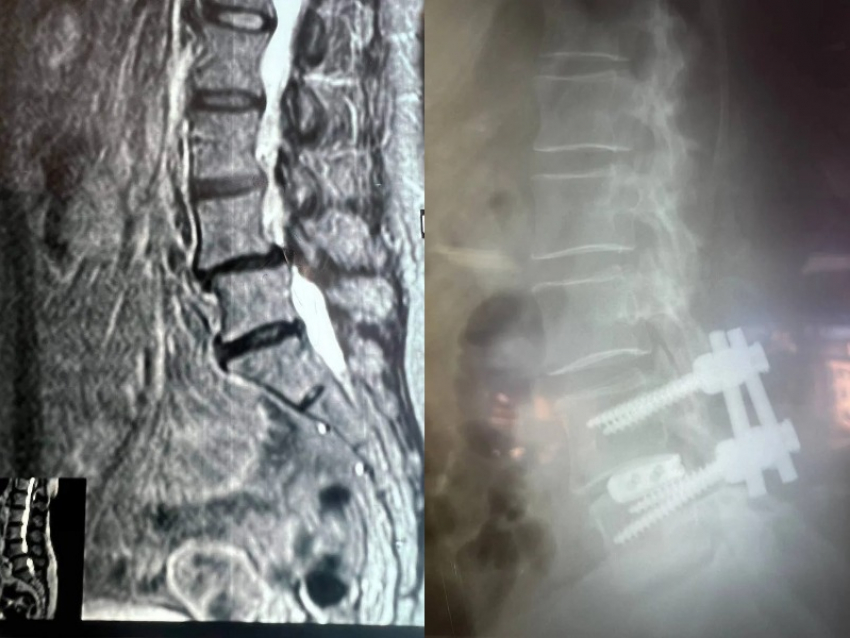

Как рассказали в пресс-службе облздрава, после всех исследований врачи выявили у пациентки множество патологий, в частности поражение межпозвоночных дисков, сужение пространства позвоночного канала на уровне 4-5 позвонков поясничного отдела и другие.

В последние месяцы боль усиливалась, резко сократилась дистанция ходьбы. В ВГКБ №11 пациентке предложили декомпрессивно-стабилизирующую операцию на позвоночнике.

«Врачи «разжали» позвонки с двух сторон, удалили грыжу и диски поражённых частей заменили на импланты. С помощью оптического прибора, микрохирургической техники и инструментария врачи избавились от компрессии защитной оболочки спинного мозга и сегментарных нервов с двух сторон. Также женщине сместили в нужное место позвонок. Для стабилизации позвоночника, врачи установили конструкцию из четырёх титановых винтов и двух балок между ними», – отметили в Минздраве.